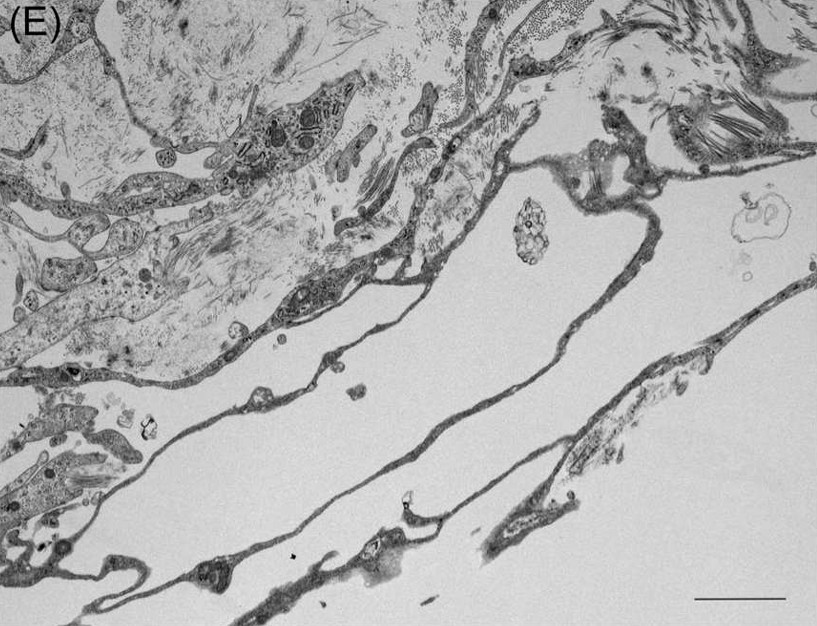

A new paper is published in the medical journal OTO Open. It is titled “Lymphatic Vessels in the Inner Ear of Patients with Meniere Disease: a Novel Pathological Finding”.

This is the first report of lymphatic vessels in the human inner ear, and this pathoogical structure is a completely new discovery. The lymphatic vessels may develop due to inflammation or decomprensation of pressure in the inner ear, suggesting that the inner ear can reactively form lymphatic vessels in some inflammation and fluid-dependent pathological coditions. The current findings help in improving our understanding of the pathogenesis of Meniere disease.